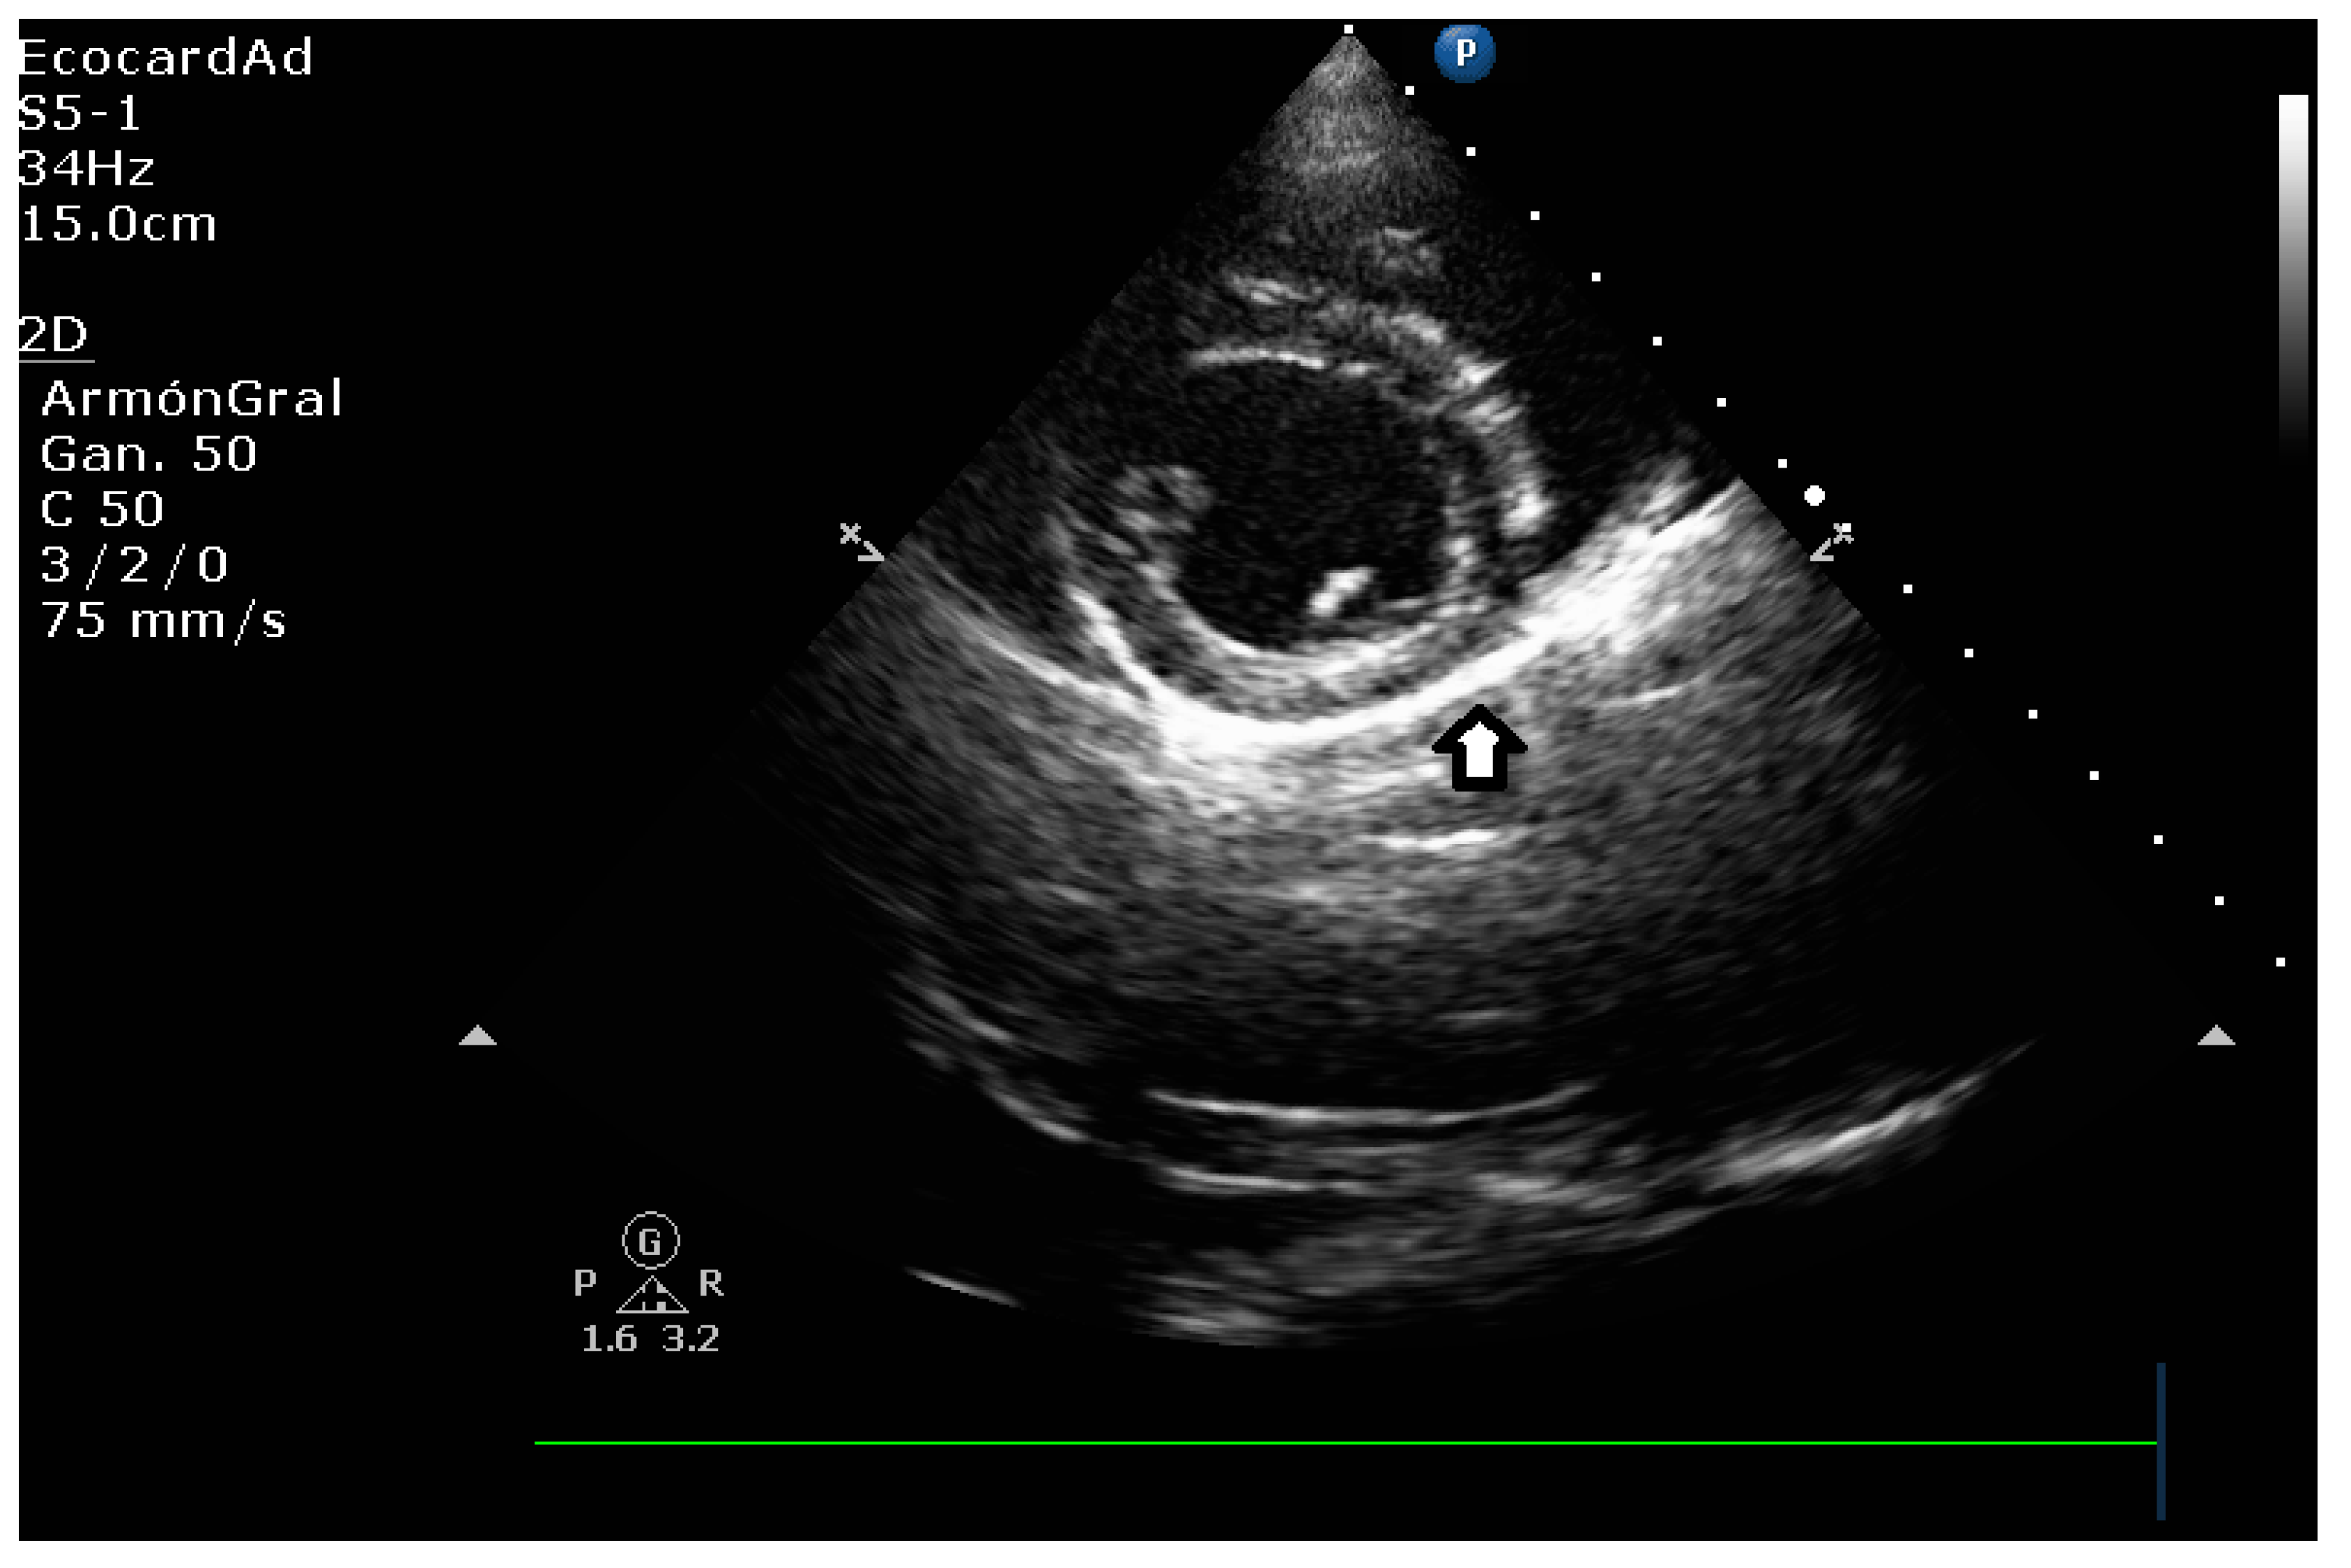

4.8.3. Degree of Myxomatous Degeneration

4.8.4. Mitral Valve Prolapse